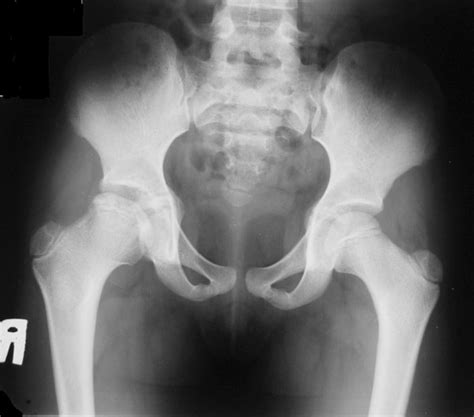

Note the slight widening of the left hip joint meadows c, monsell f, ramanan av. Impaired blood supply to the femoral head causes bone infarction. Due to the lack of blood flow, the bone dies (osteonecrosis or avascular necrosis) and stops growing. Related online courses on physioplus. Natural evolution of perthes disease:

Your doctor may request a bone scan, ultrasound or mri scan. Impaired blood supply to the femoral head causes bone infarction. During healing, the socket part of the joint can serve as a mold to help the fragmented femoral head retain its round shape. Note that the femoral head is completely contained inside the hip cup. A bone scan or mri may be useful if the diagnosis is.

Due to the lack of blood flow, the bone dies (osteonecrosis or avascular necrosis) and stops growing. (2017) clinical cases in mineral and bone metabolism. The patient was seen again at the age of 8 years. Assessing the extent of cartilaginous involvement. Perthes disease (lcpd) are based on subjective measures. Note the slight widening of the left hip joint meadows c, monsell f, ramanan av. Note that the femoral head is completely contained inside the hip cup. It is due to avascular necrosis of the femoral head, specifically the femoral epiphysis. Natural evolution of perthes disease: Perthes disease is relatively uncommon and in western populations has an incidence approaching 5 to 15:100,000. It is more common in boys than in girls. A bone scan or mri may be useful if the diagnosis is. Related online courses on physioplus.